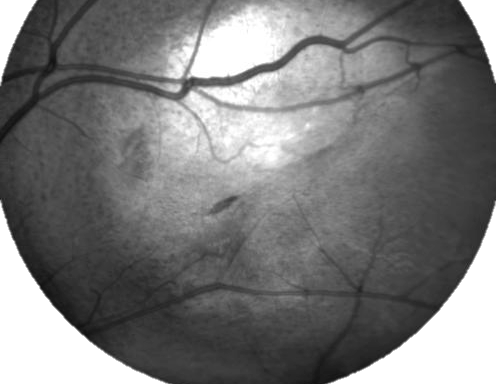

GAP. A phase I escalating dose of subretinal sodium iodate: a toxi-induced animal model of geography atrophy of RPE and phtotoreceptors 26/03/2013

The objective of this study is to establish an animal model of geographic atrophy of the outer layers of the retina limited to a certain area of the fundus to resemble geographic atrophy secondary to age-related macular degeneration and Stargardt’s disease, by using a toxic compound specific for retinal pigment epithelium. This model will be used to test different regenerative therapy approaches such as the use of stem cells and retinal transplants and to test nanotechnology approaches within the context of tissue recovery.